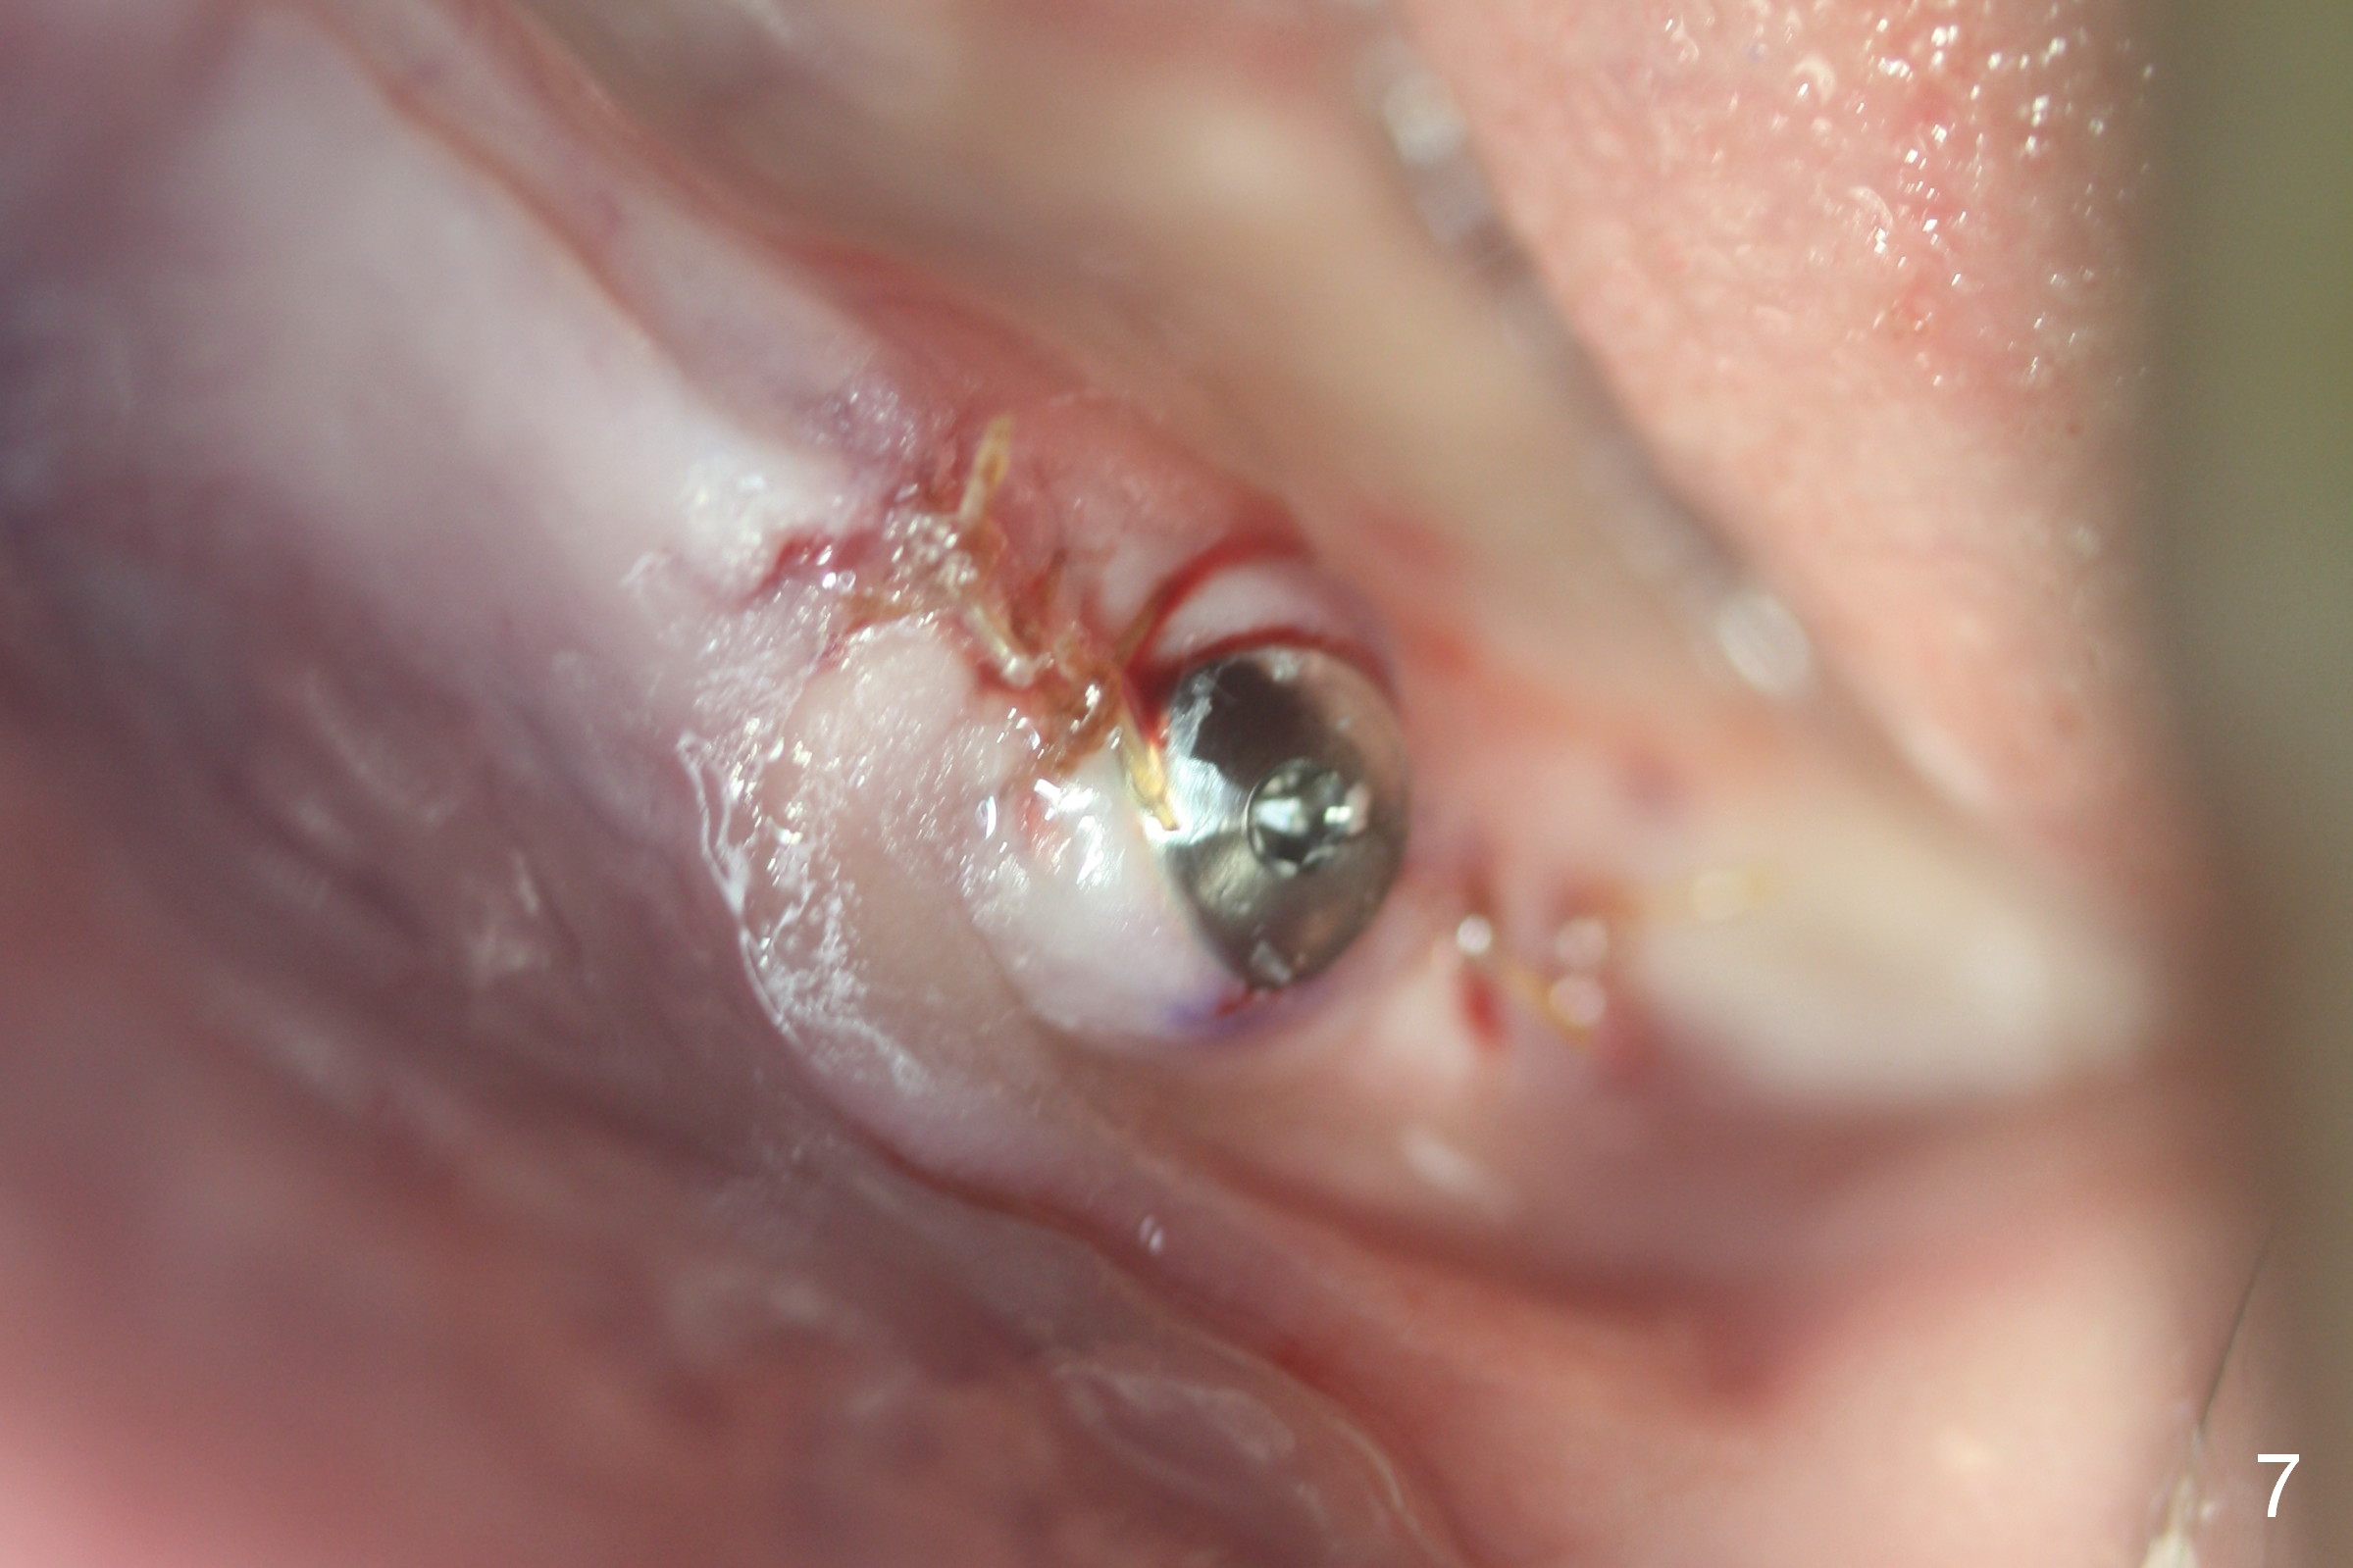

Except the tooth #30, the patient is completely edentulous (Fig.1,2). His chief complaint is "food gets into the missing tooth area". Due to short guide pin (Fig.3) and parallel pin (Fig.4), it is difficult to calculate precisely at the site of #19 the distance to the superior border of the Inferior Alveolar Canal (Fig.4 red dashed line). The clearance appears to be limited when a 4.3 mm drill is in place with 11 mm depth (Fig.5). Therefore an implant shorter than the last drill is placed (5x9 mm, Fig.6). Insertion torque is >50 Ncm. A 5x4(2) mm pair abutment is inserted temporarily to check occlusion with the opposing dentition (A). Finally a 5x2 mm healing abutment is placed with harvested autogenous bone placed between the implant and abutment (Fig.7). Before discharging the patient, the lower RPD is in place to check the position of the implant/abutment (Fig.8).